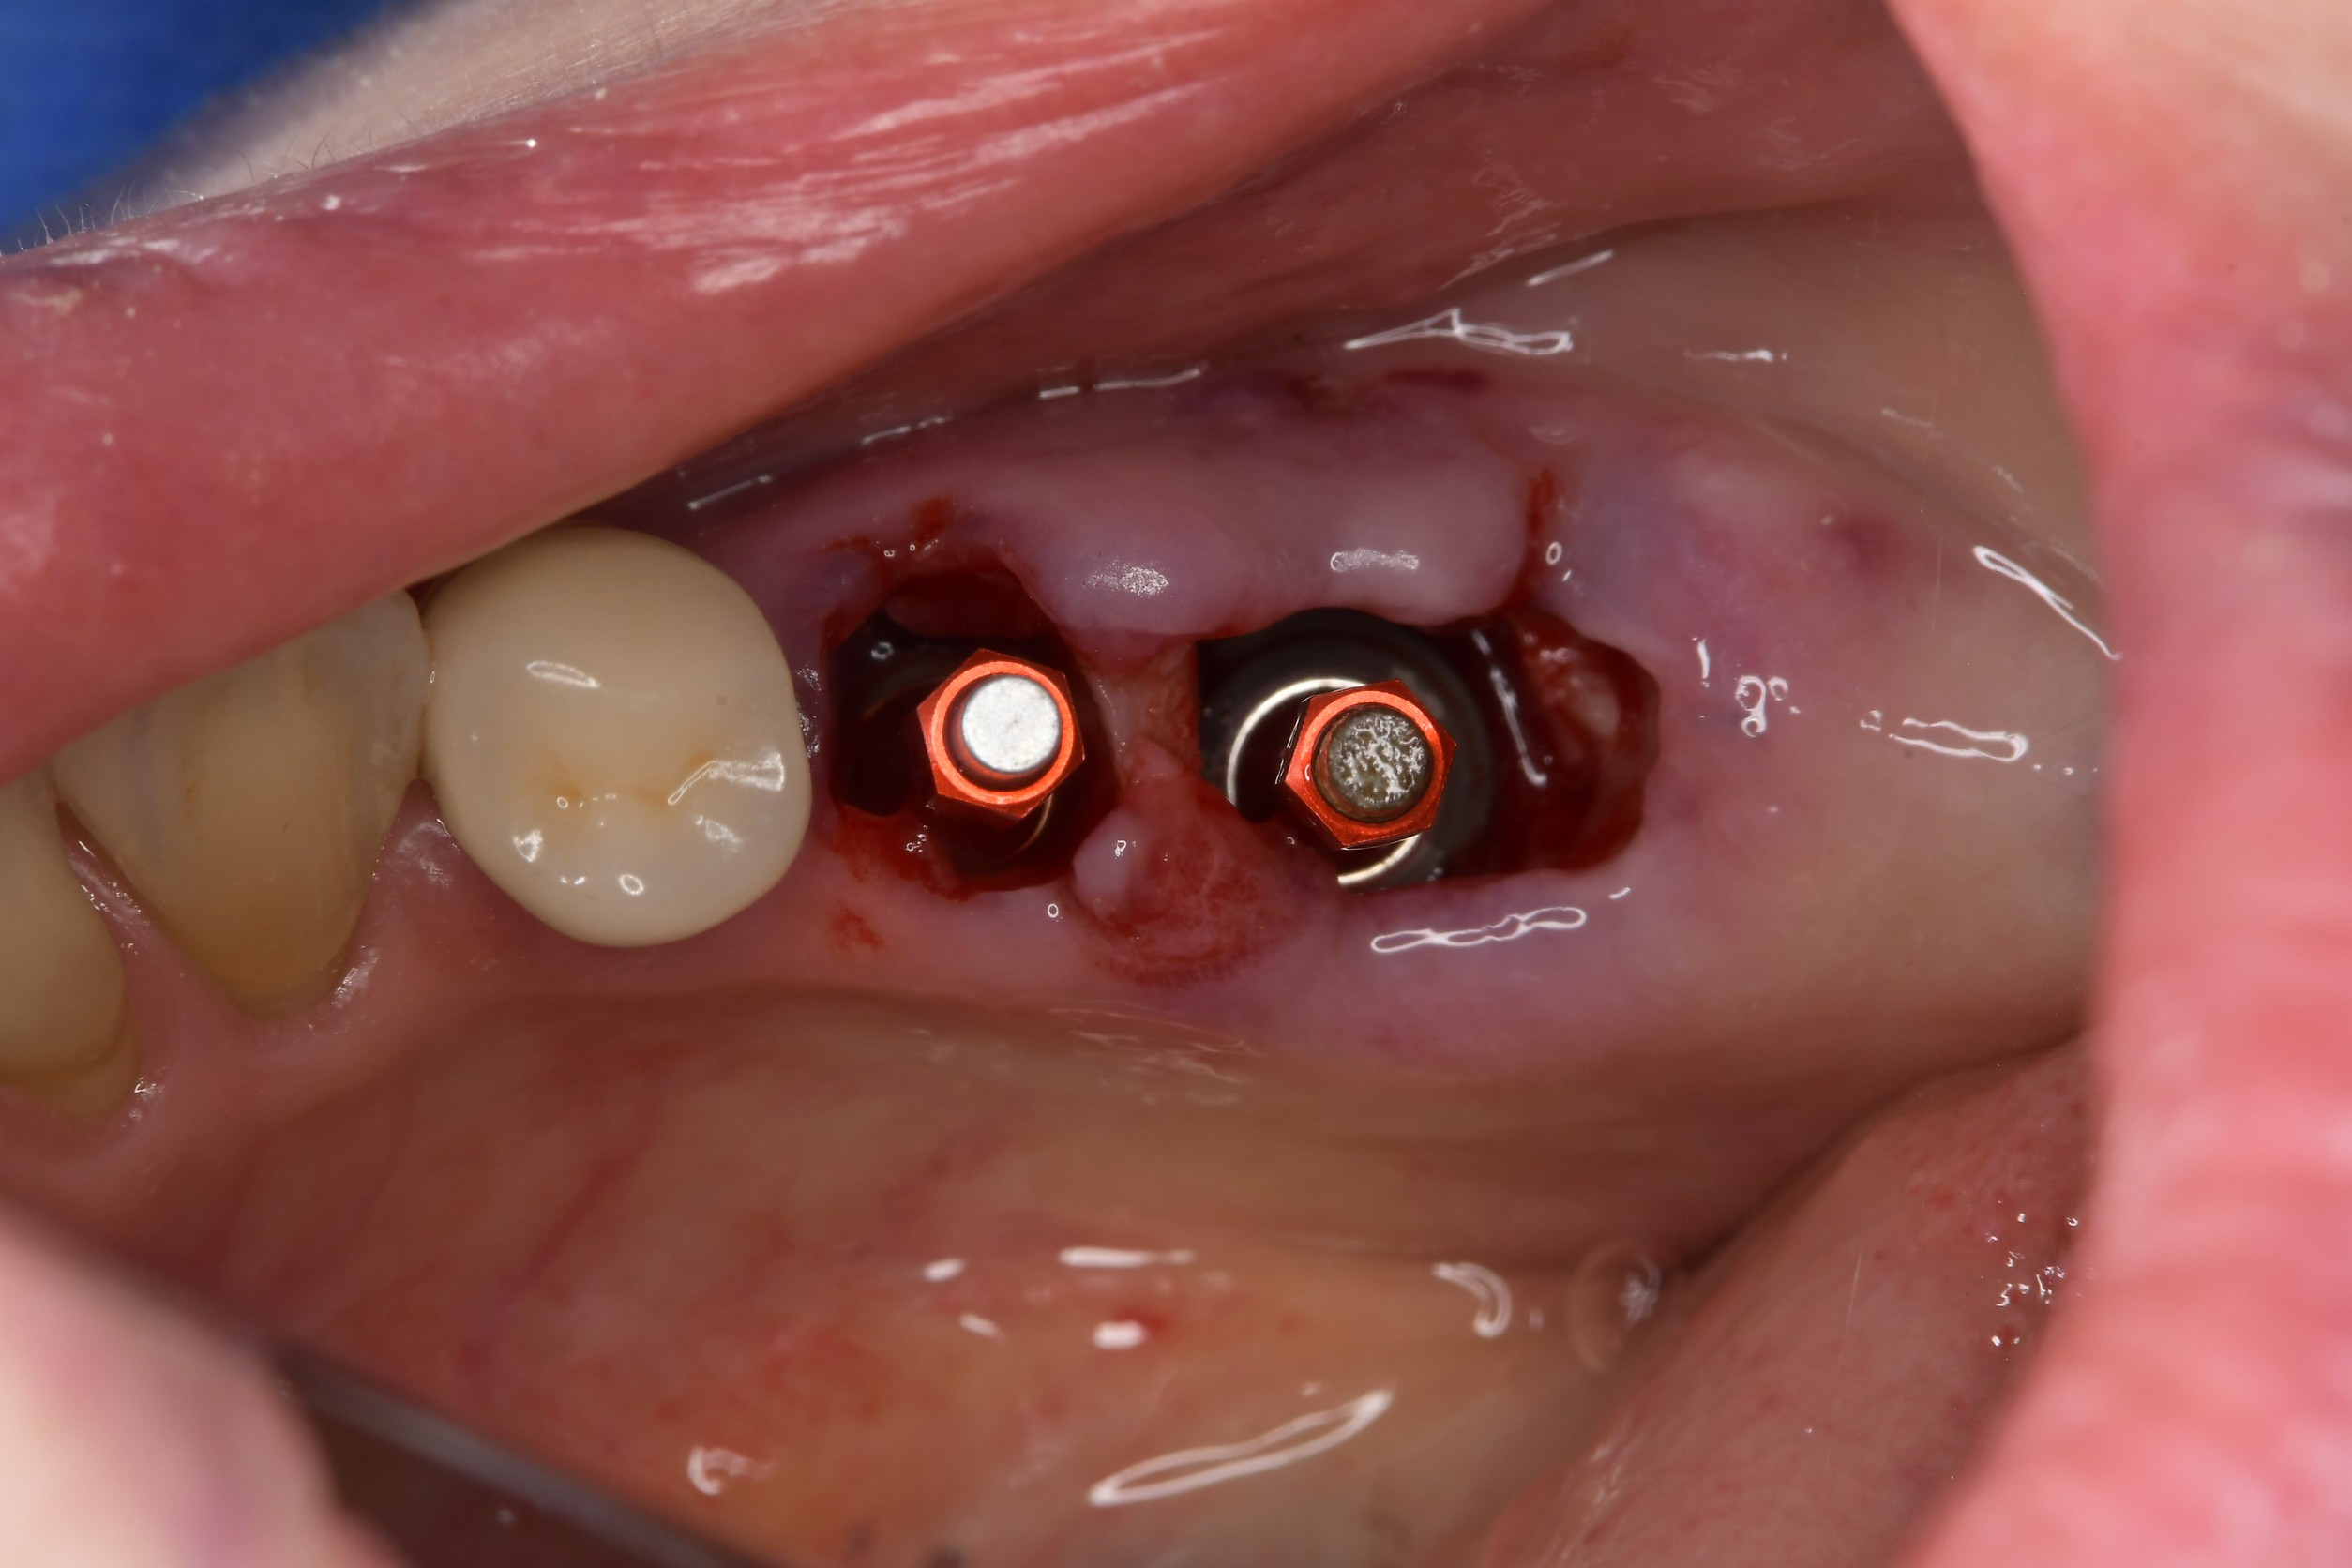

身体への負担を考慮した「抜歯即時埋入」

しかし、当院では「抜歯即時インプラント埋入」を採用しました。

これにより、歯ぐきを切開したり縫合したりする必要がなく、治療期間と回数を短縮することが可能になります。

手術当日は、患者さんの不安を抑えるため、スピードと正確性を追求しました。

当日の流れ(約60分で終了)

2. 局所麻酔・抜歯

3. インプラント埋入(切開なし)

これらすべてを終えてお帰りいただくまで、わずか60分ほどです。

手術から10日後の検診では、抜歯した部分の歯ぐきはすでに良好な状態まで回復していました。

術後の経過写真からも、切開を行わない処置であったため、出血や腫れ、術後の痛みが比較的少ない状態で経過していることが確認できます。外科処置を一度で終えられた点は、お仕事や家事で忙しい患者さんにとって負担軽減につながりました。